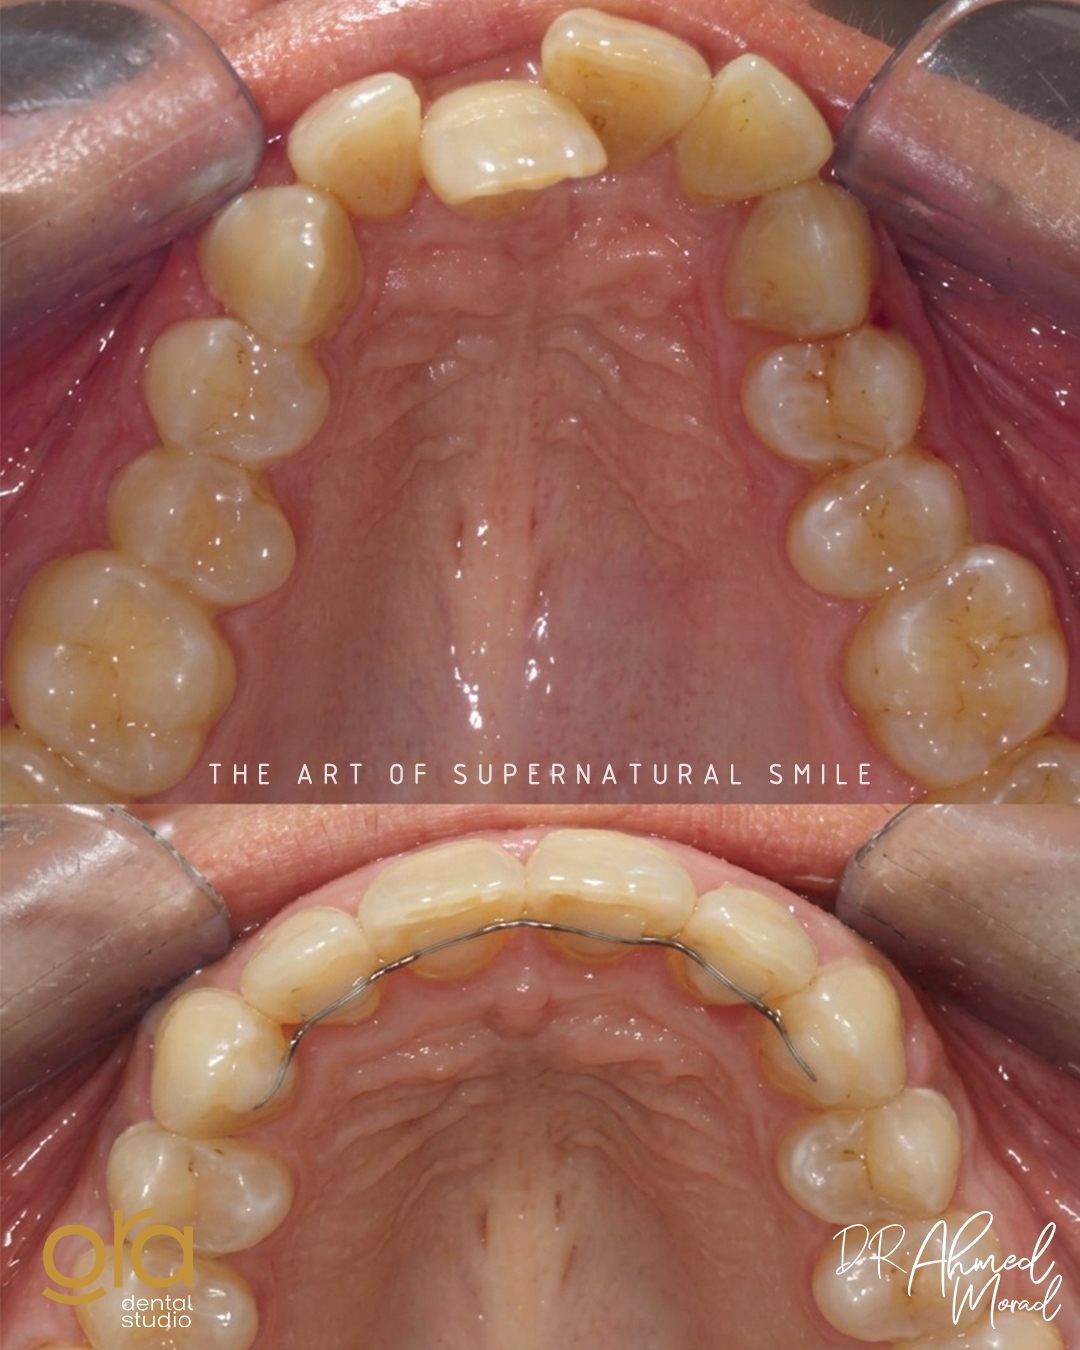

تقويم الأسنان

ابتسامتك المثالية تبدأ من انتظام أسنانك وتناسقها، وهذا ما نحرص عليه في ORA Dental Studios. فالتقويم ليس مجرد إجراء جمالي وحسب، بل هو علاج متكامل يعيد لأسنانك موقعها الصحيح ويحافظ على صحة فمك ولثتك. بفضل تقنيات التقويم الحديثة، أصبح بإمكانك الحصول على ابتسامة جذابة ووظيفة فموية سليمة بسهولة وراحة، مع نتائج تدوم لسنوات طويلة.

تقويم الأسنان في ORA Dental هو إجراء علاجي وتجميلي يهدف إلى تصحيح وضعية الأسنان والفكين باستخدام أجهزة متخصصة، سواء كانت معدنية تقليدية، أو خزفية جمالية، أو تقويم شفاف غير مرئي. يعمل التقويم على تحسين تناسق الأسنان، وتسهيل عملية المضغ والنطق، والحفاظ على صحة الفم والأسنان على المدى الطويل.

- تصحيح تزاحم الأسنان واعوجاجها.

- تحسين النطق وتسهيل المضغ.

- المساعدة في الحفاظ على صحة اللثة والأسنان.

- الوقاية من تآكل الأسنان غير المنتظمة.